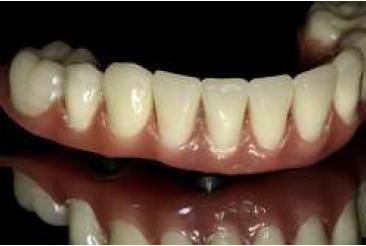

Al tercer día se realizó la instalación con torque manual y ajuste oclusal (figs. 13,14,15,16).

A los 10 días, luego de la cirugía, se citó a la paciente a control para realizar la retirada de la sutura11; se dio torque a los tornillos protésicos (10 N/cm) y se chequeó la oclusión nuevamente. Se ha seguido controlando a la paciente cada 6 meses, hasta cumplir 2 años desde la fecha de instalación de la aparatología, sin manifestar complicación alguna (figs. 17, 18, 19, 20, 21).